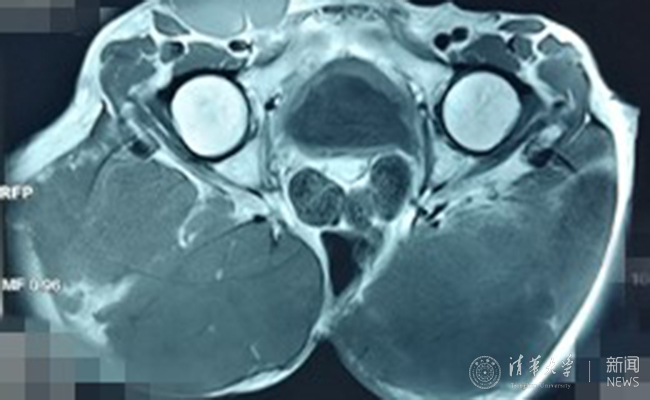

患者术前影像资料。

第7次手术后两年,骶骨脊索瘤再次复发,患者已经失去了治疗的信心,选择消极应对,“不想再拖累老伴儿和孩子们了”。在接下来的4年时间里,肿瘤疯长,像两个巨大的肉球,挤压着臀部的肌肉和神经,走路都迈不开腿、睡觉无法平卧,最终导致小便失禁、大便无力,肿瘤的肿胀感也让患者无法安眠。